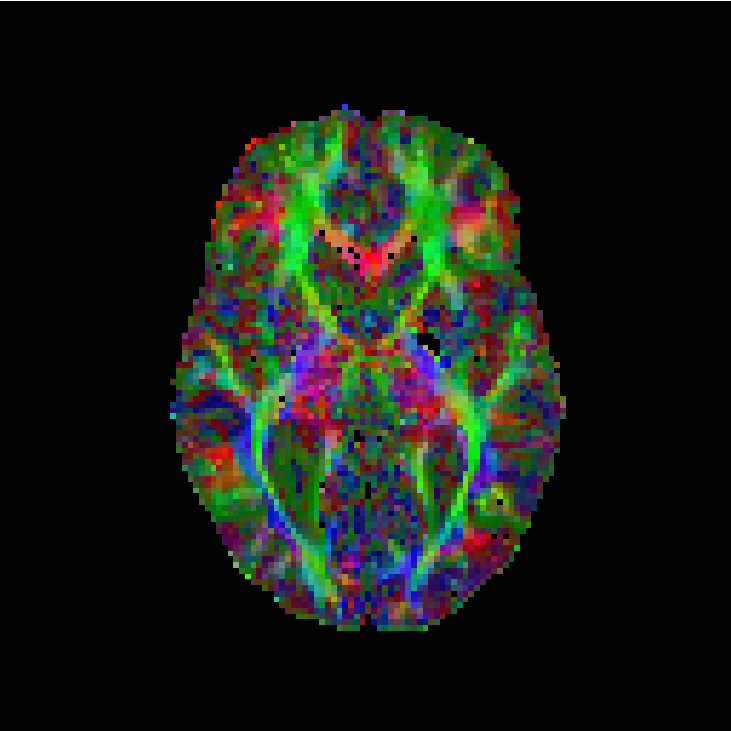

The numerical results are in Table 1 and Figures 3–5, with the first of the figures showing the colour-coded principal eigenvector of the reconstruction, the second showing the fractional anisotropy and principal eigenvectors, and the last one the errors in the latter two, in a colour-coded manner. All plots are masked to represent only the non-zero region. The field of fractional anisotropy is defined for a field of 2-tensors on as

As we can see, the non-linear approach (3.2) performs overall the best by a wide margin, in terms of the pointwise Frobenius error, i.e., error in . This is expressed as a PSNR in Table 1. What is, however, interesting, is that the constraint-based approach (3.5) has a much better reconstruction of the principal eigenvector angle, and a comparable reconstruction of its magnitude. Indeed, the 95% confidence interval in Figure 3(g) and Figure 4(g) suggests a nearly perfect reconstruction in terms of smoothness. But, the Frobenius PSNR in Table 1 for this approach is worse than the simple unregularised inversion by regression. The problem is revealed by Figure 5(f): the large white cloudy areas indicate huge fractional anisotropy errors, while at the same time, the principal eigenvector angle errors expressed in colour are much lower than for other approaches. Good reconstruction of the principal eigenvector is important for the process of tractography, i.e., the reconstruction of neural pathways in a brain. One explanation for our good results is that the regulariser completely governs the solution in areas where the error bounds are inactive due to generally low errors. This results in very smooth reconstructions, which is in the present case desirable as our synthetic tensor field is also smooth within the helix.

The results are in Table 2 and Figures 6–8, again with the first of the figures showing the colour-coded principal eigenvector of the reconstruction, the second showing the fractional anisotropy and principal eigenvectors, and the last one the errors in the latter two, in a colour-coded manner. Again, all plots are masked to represent only the non-zero region. In the figures, we concentrate on error bounds based on 95% confidence intervals, as the results for the 90% and 99% cases do not differ significantly according to Table 2.

This time, the linear approach (3.3) has best overall reconstruction (Frobenius PSNR), while the nonlinear approach (3.2) has clearly the best principal eigenvector angle reconstruction besides the regression, which does not seem entirely reliable regarding our regression-based pseudo-ground-truth. The constraints based approach (3.5), with 95% confidence intervals is, however, not far behind in terms of numbers. More detailed study of the corpus callosum in Figure 8 (small picture in picture) and Figure 7 however indicates a better reconstruction of this important region by the nonlinear approach. The constrained approach has some very short vectors there in the white region. Naturally, however, these results on the in vivo data should be taken with a grain of salt, as we have only a somewhat unreliable pseudo-ground-truth available for comparison purposes.